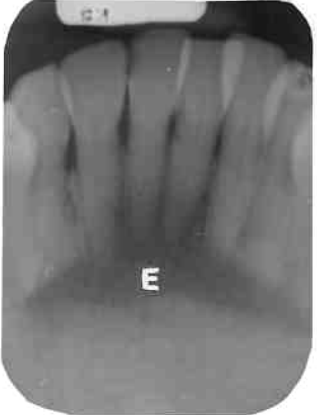

16. What is showing by E?

17. What is showing by arrow?